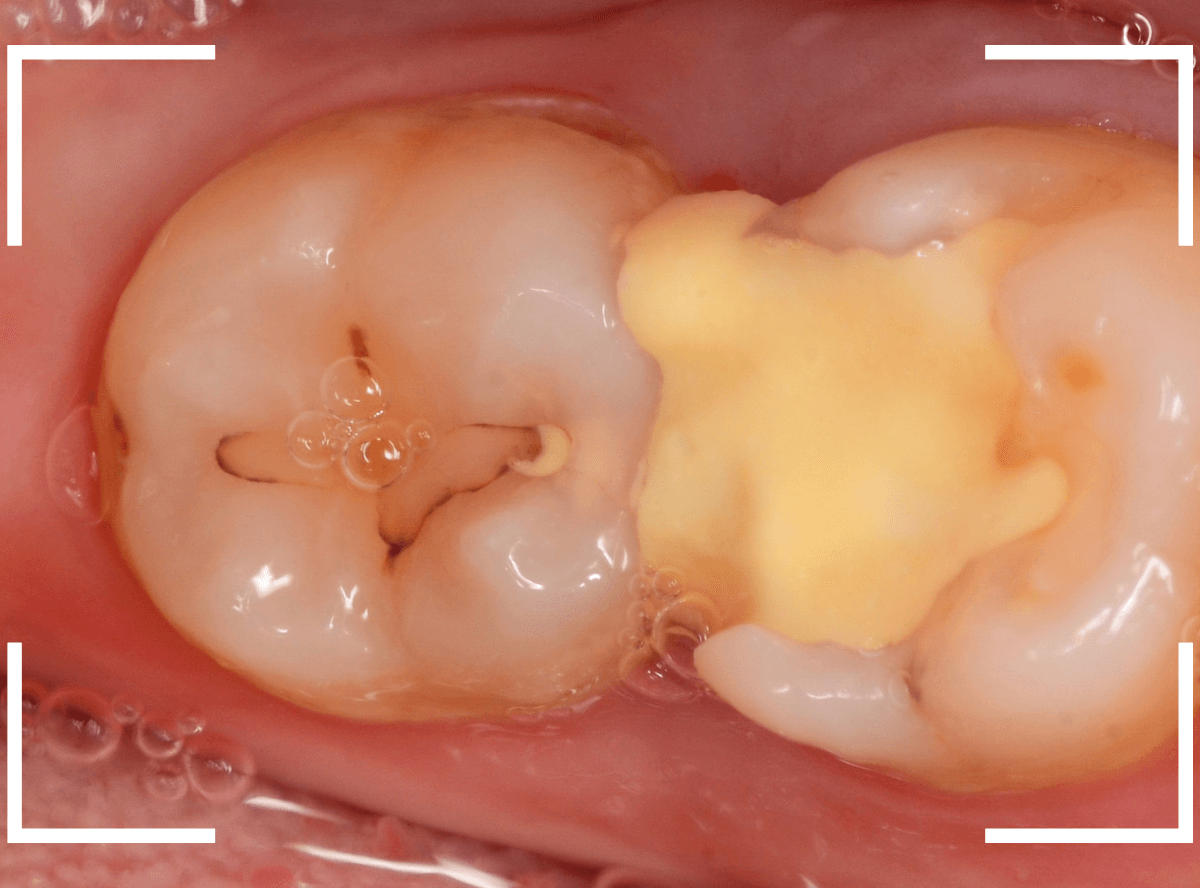

Case.24 レジンの下で虫歯が進行

上の奥歯の虫歯が見つかった患者さんです。

初診のチェックの際に、上から目視すると、レジンがつめてある〇部分が薄暗く黒くなっているので、これは虫歯があるな、とわかりました。

レントゲン写真で確認します。

治療を開始します。

先ほどの黒く見えた部分は少し削るとすぐに虫歯が出てきました。

手前の歯まで虫歯を除去した時点で、う蝕検知液で確認します。

赤く染色されている部分が虫歯です。

思ったよりも深めの虫歯ですね。

レジンを除去して虫歯をすべて治療したところです。

レジンの中も全体にうっすらと虫歯になっていました。

このくらいの虫歯でも、患者さんは自覚症状はありませんでした。

ご自身の自覚症状だけでは、虫歯の状況がわからないですし、自然に虫歯が治る事もありません。

いつものお話ですが、定期的なメンテナンスで、虫歯の早期発見・治療を心がけましょう。